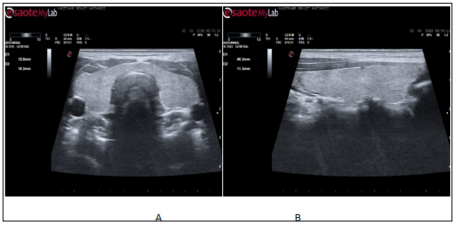

Our study was carried out retrospectively with ultrasonographic archive scanning. The thyroid ultrasound in 30 mothers was performed at the 9th months of gestation, and also 6th and 12th months after delivery, to calculate thyroid volume. The results were compared with the control group of women who had not delivered in the last year. The subjects who detected thyroid lesion on ultrasonography were not included in the study.During the ultrasonographic examination, the subjects rested in a supine position with their necks slightly extended. The mediolateral dimension of both lobes was measured on the transverse image (Figure 1a). The craniocaudal and the anteroposterior dimensions were measured on the longitudinal image (Figure 1b). The volume of each lobe was estimated in cubic centimeters using the equation of Brunn et al. [5].

Figure 1: Ultrasound image (and line diagram) of the thyroid gland on transverse (a) and longitudinal (b) scans showing the measurement planes.